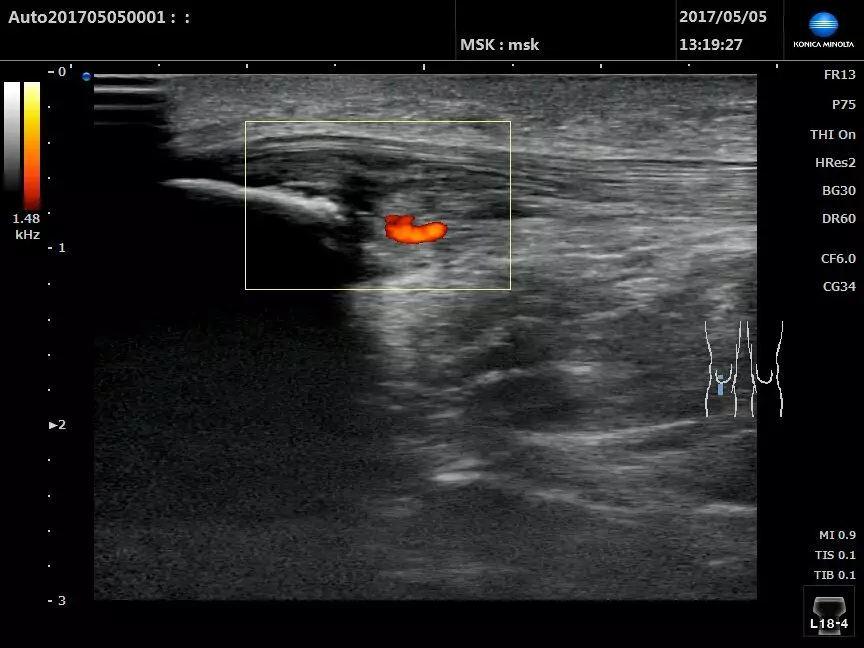

如病變部位除能看到相關二維圖像改變以外,還能探測到彩色或能量多普勒血流信號時,則提示該病變處于炎癥活動期,往往多普勒信號多少與炎癥充血程度呈正相關,與患者的疼痛感有密切關聯。